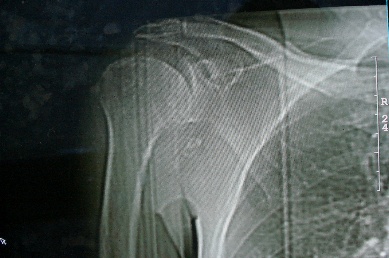

右上肢活动不便多年,最近加重。右肱骨肿瘤,请会诊!

骨软骨瘤恶变可能性大

右肱骨近断骨软骨瘤伴临近关节退变.有无恶变建议进一步检查.

右肱骨近断骨软骨瘤伴临近关节退变。

病变边缘轮廓清晰无骨质破坏,邻近软组织不肿胀,不支持肿瘤恶变。